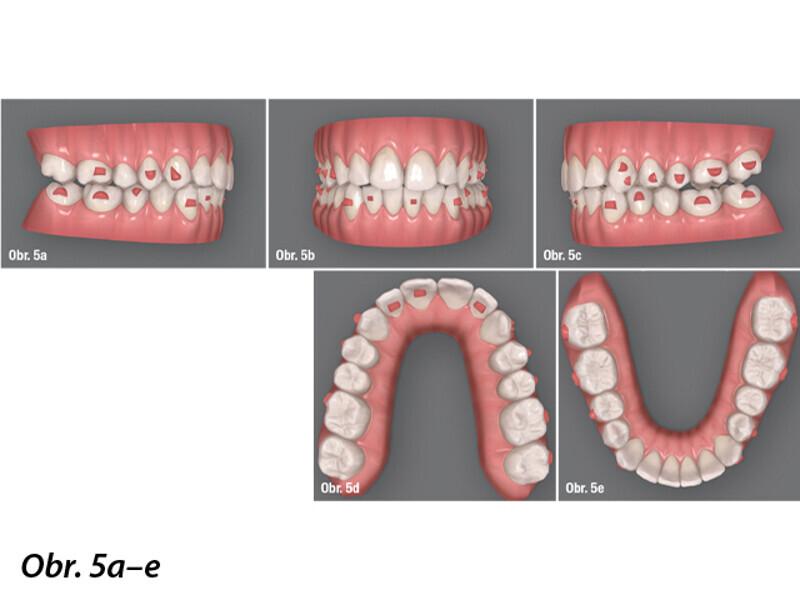

Ortodontická léčba komplexních případů malokluze pomocí průhledných alignerů